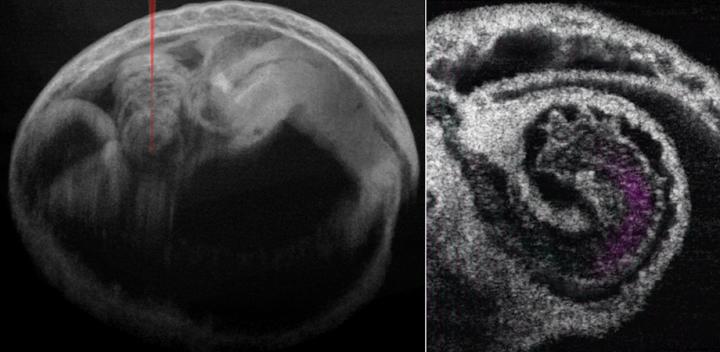

Mouse Embryo and Heart with Blood Flow

image: Mouse embryo and heart with blood flow. Wang and Larina, doi 10.1117/1.JBO.25.8.086001. view more

Credit: Wang and Larina.